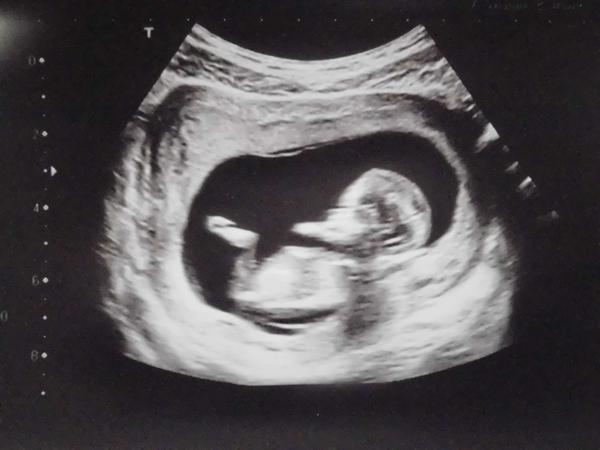

@makuka88 Tak to má být Marti, to jen značí, že je mimi v pořádku 🙂 Jinak mě zas pobolívá pravá strana a to k tomu prostě patří 😒 Ale přejde to 🙂